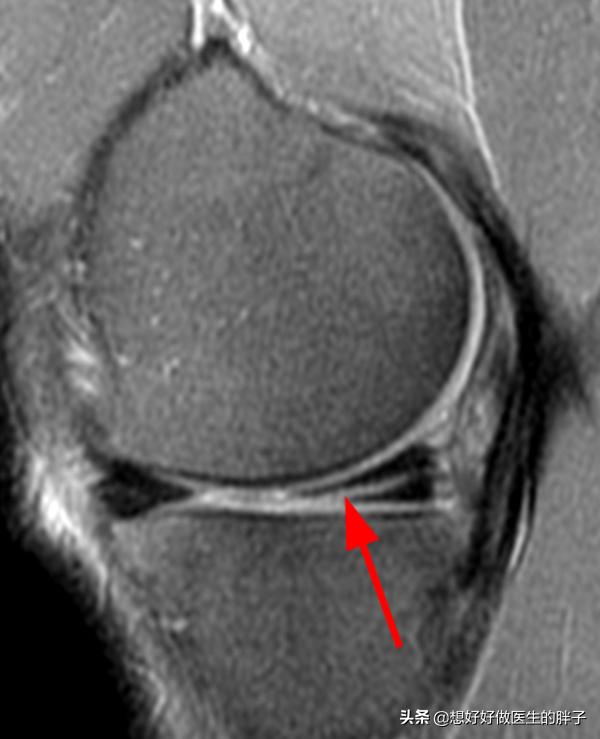

●A层裂:为什么叫层裂呢?大家可以看到半月板损伤的位置,在于半月板的白区,而且有了明显的裂开,像分层了一样,如果分层的范围比较大,有可能会累积有血供的滑膜缘。这种情况在核磁上是这样子的。

如果是层裂,因为有很大一部分是位于白区,这里没有血供,自我愈合的可能性特别低,如果是年轻人在撕裂的滑膜缘有可能有部分的愈合,但是在白区几乎没有愈合的可能性。这种情况一般要进行关节镜下的手术治疗,将没有可能愈合的半月板内侧进行修整,有可能愈合的红白区和白区给予缝合,大家看下图就会明白A是半月板明显的层裂,经过修整以后,尝试给与其进行缝合,图D即为缝合之后的影像学资料。